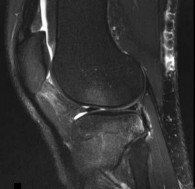

Question 9:

The radiograph describes a Segond fracture, which is an avulsion fracture of the anterolateral aspect of the proximal tibia. It is typically associated with avulsion of the anterolateral ligament (ALL) or lateral capsular attachments and is highly predictive (pathognomonic) of an anterior cruciate ligament (ACL) tear.